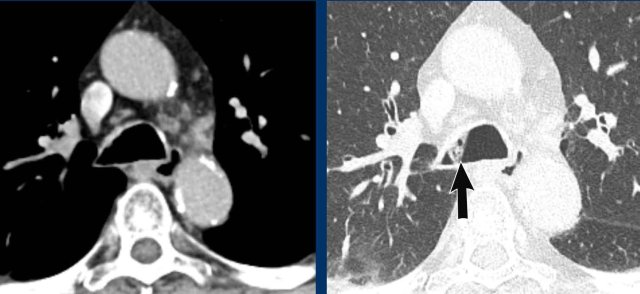

Image

The PET-CT shows high uptake corresponding to a small nodular

lesion in the proximal trachea in a 52 y.o female with prior colorectal

cancer.

PA: metastasis of colorectal cancer.